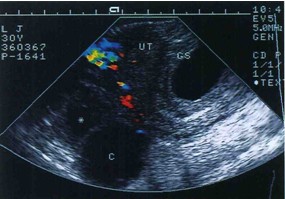

图4妊娠合并黄体囊肿

子宫增大,内见胎囊,子宫右侧见圆形囊肿,壁薄,囊液清亮